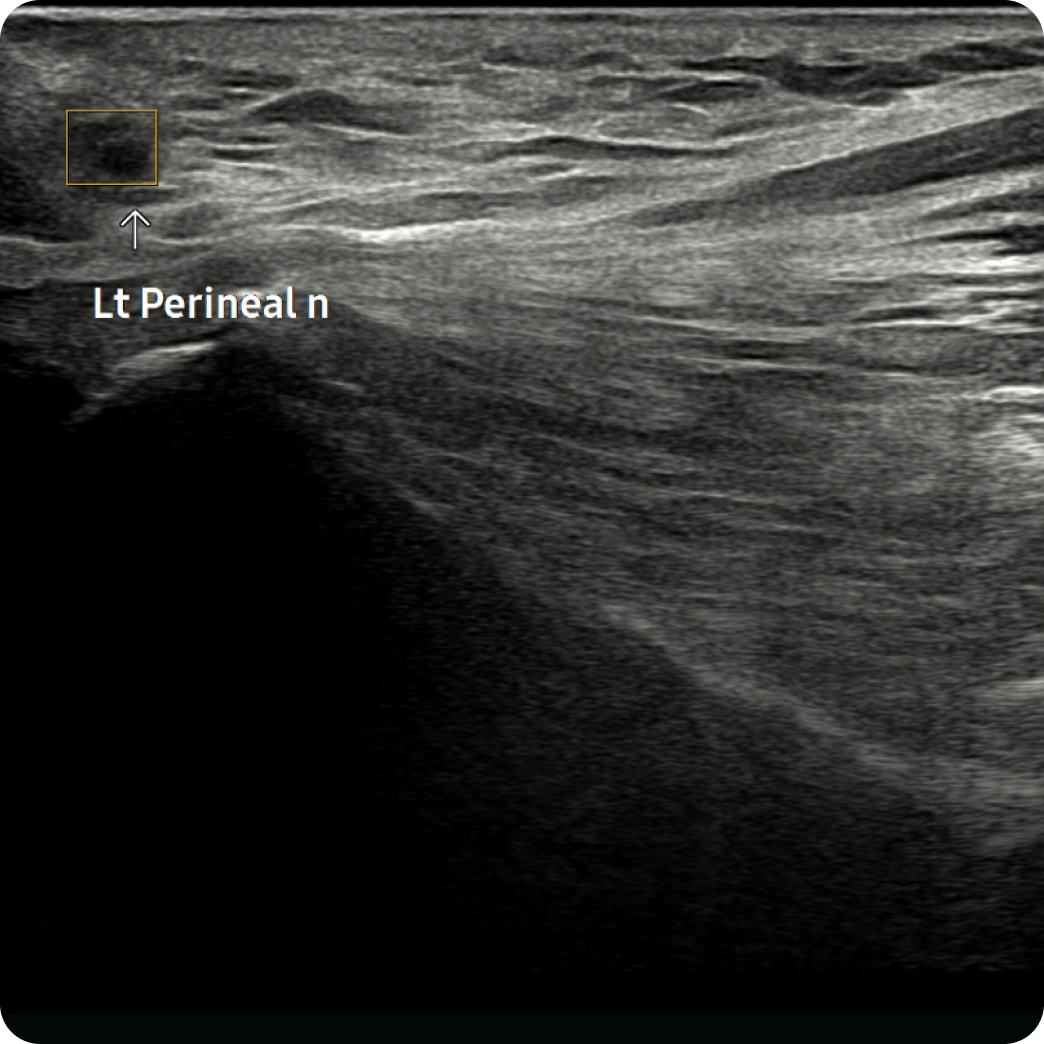

초음파 검사

초음파를 통해 회음부 주변의 신경주행, 연부조직 상태를 직접 확인합니다. 회음신경의 손상이 있는 경우 nerve track 기능으로 신경 단면을 확인했을 때 손상을 객관적으로 확인할 수 있습니다.